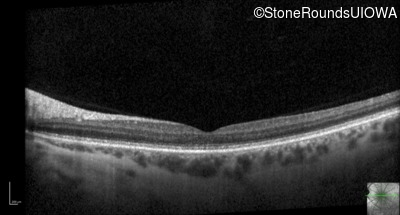

Optical Coherence Tomography - Right - 20/40

Exemplar / OCT Stack

Optical Coherence Tomography - Left - 20/25